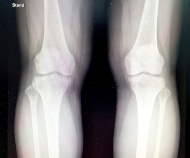

연골은 부드러운 움직임을 위해 뼈 사이에 존재하는 결합 조직으로 인간의 근골격계를 구성하는 중요한 요소 중 하나입니다. 연골은 충격을 흡수하고 뼈 마찰을 줄여 관절 부상을 예방합니다. 또한 연골은 관절에서 분비되는 활액에 영양분을 공급받아 영양분을 흡수해 생존한다. 그러나 나이가 들어감에 따라 연골 조직이 퇴화하고 내구성과 탄력성이 떨어지게 되어 관절염과 같은 상태로 이어질 수 있습니다.

무릎은 몸을 지탱하고 움직이는 중요한 역할을 합니다. 이러한 기능을 수행하는 것은 힘든 작업이며 이러한 기능을 수행하는 무릎 관절은 매우 복잡합니다. 따라서 무릎은 가장 취약한 부위 중 하나입니다. 무릎연골손상은 무릎관절에 연골손상이 발생하는 상황입니다. 이는 여러 가지 이유로 발생할 수 있습니다.